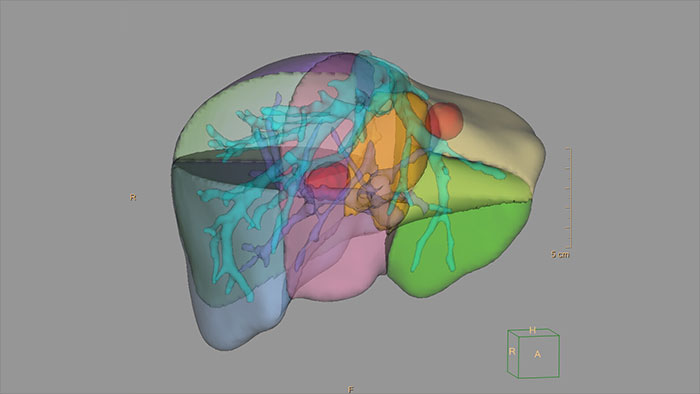

- 3D Modeling

3D Modeling

Streamlined modeling workflow

Allows to view volumetric images of anatomical structures, perform segmentation, edit and combine segmented elements (tissues) into a 3D model.

Benefits

- Studies of CT & MR can be used for creating a single 3D model of the same patient. The application provides tools that allow the user to align between the volumes of interest in the images.

- 3D Modeling batches files can be easily exported in standard formats such as STL, with the option to also provide a 3D PDF as an additional means for results sharing with 3D printing or other services* .

- The user may determine the information related to the exported elements of the 3D model such as smoothness and output mesh size.

- Contours can also be exported as RT Structures.

*3D models are not intended for diagnostic use.